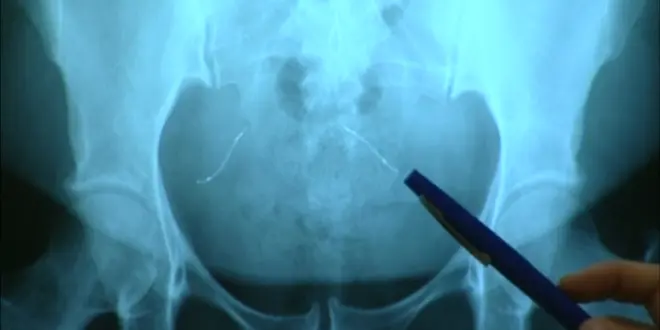

Pour cette opération, il n’existe pas de règle générique. Le type d’ablation, le mode opératoire (cœlioscopie, voie vaginale ou laparotomie) et les éventuels effets secondaires et hormonaux d'une telle chirurgie doivent être discutés, au cas par cas, entre la patiente et son médecin. Un acte d’imagerie (radio ou IRM) permet d’abord de localiser les implants en cas de migration.